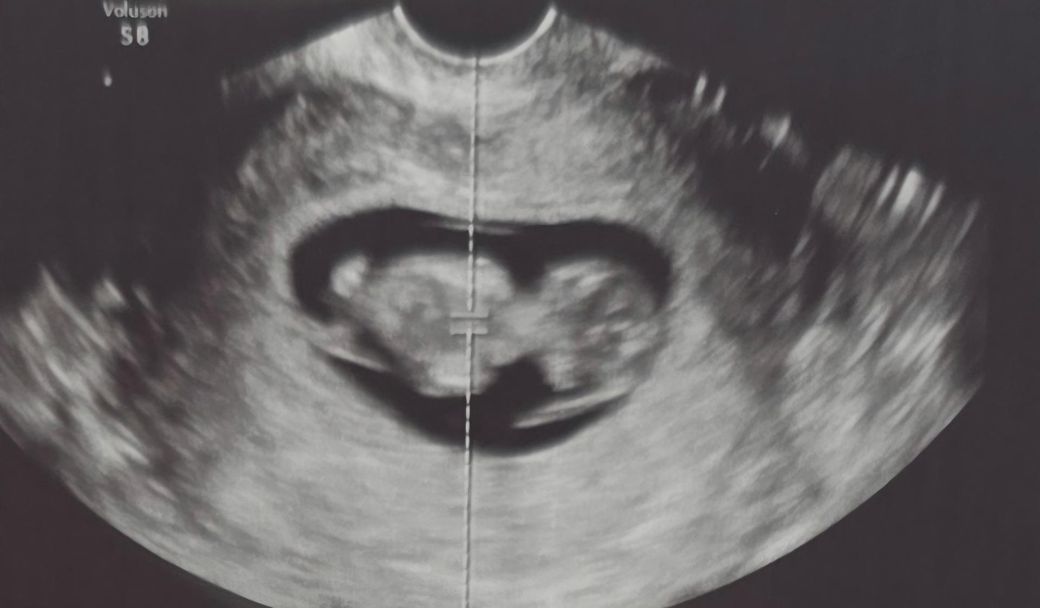

• 2번 째 사진

올려주신 영상에서는 태아 주변으로 피하 부종처럼 보일 수 있는 저에코 영역이 약간 두꺼워 보이기는 합니다. 다만 단일 이미지로 확정적으로 “태아수종이다”라고 진단할 수 있는 수준은 아닙니다. 실제 진단은 다음 기준이 필요합니다. 흉수, 복수, 심낭삼출 중 최소 두 가지 이상이 동반되어야 태아수종으로 정의됩니다. 현재 사진만으로는 그 정도까지는 명확히 확인되지 않습니다.